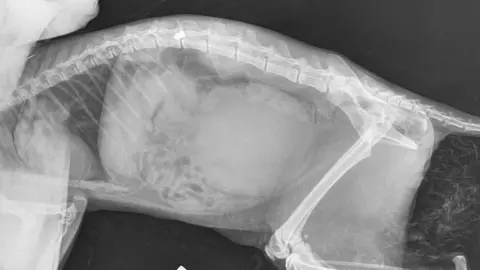

X-rays of his injuries showed he had been "shot in his spine" so his owners made "the devastating decision to have him put to sleep, as nothing more could be done to help him", she added.